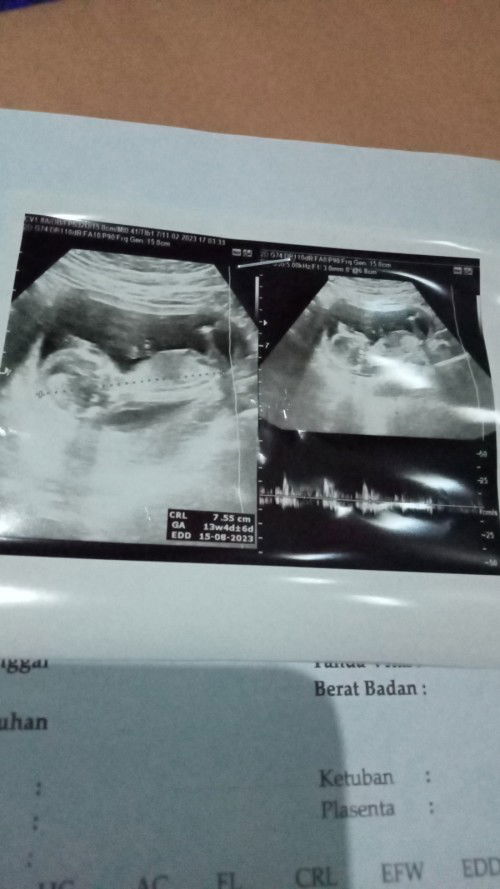

kalau kata dokter normal berarti aman aman aja bun.. crl = ukuran panjang janin 7.55cm GA = ukuran kehamilan 13 minggu 4 hari edd = perkiraan lahir 15 agustus 2023